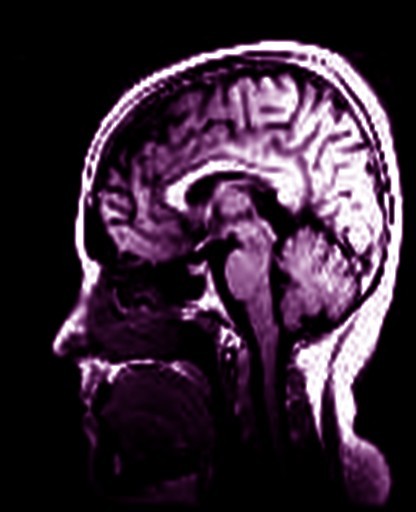

My brain's latest photo shoot.